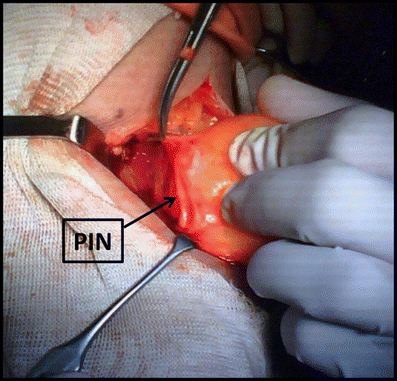

The incision of the supinator muscle exposed a fatty mass

The dissection of the mass revealed that it is constricting the PIN